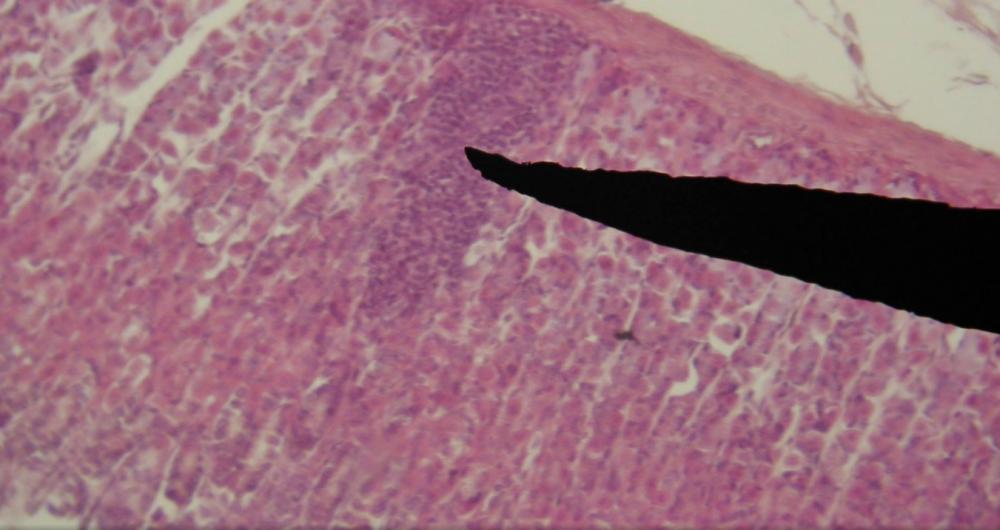

enterocyt (jelito cienkie, czcze)

komórka kubkowa (jelito cienkie, czcze)